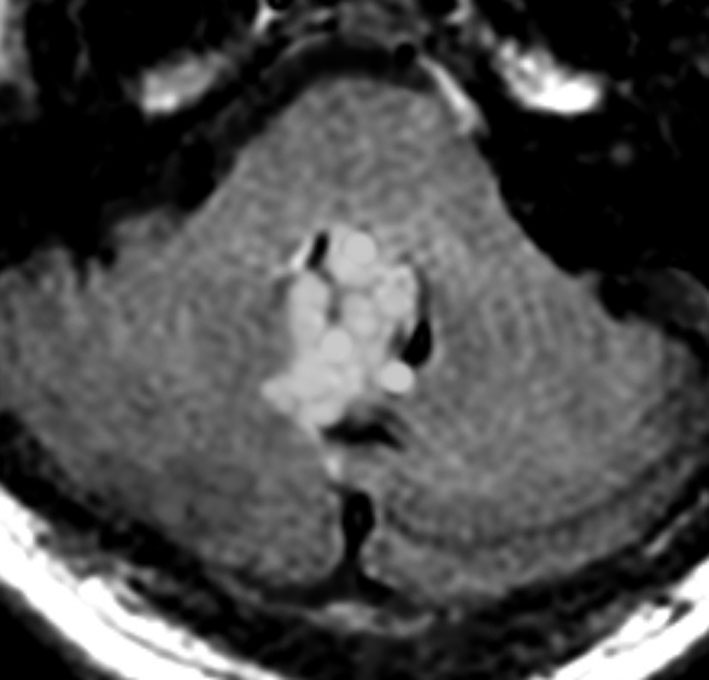

画像所見

- 比較的境界明瞭な固形腫瘍です

- T2強調画像で高信号,T1では低信号で,部分的にガドリニウム増強されます

- 小脳内の離れた部位に結節を作ることがあります

- 成人の毛様細胞性星細胞腫に似ている所見と言えます

偶然に発見された無症状の例

1990年代に無症状で発見され生検術を行った20代男性の例です。その後20年近く観察しましたが増大しませんでした。